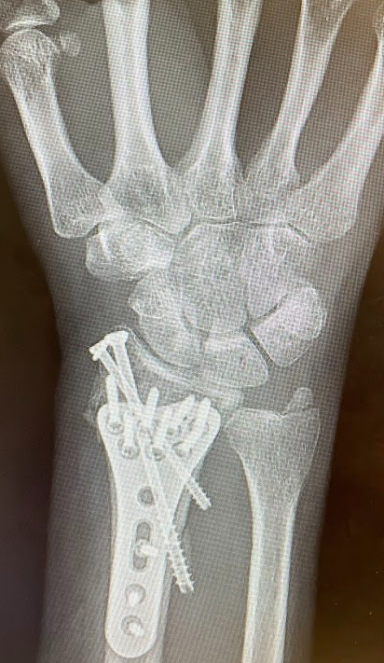

In this series, medical scans—MRI images, X-rays, and other diagnostic views—are transformed into intimate portraits that merge the clinical with the deeply personal. Each work intertwines medical imagery with biographical details, creating a layered visual narrative that honors both the physical realities of illness and the inner lives of those who endure them.

The exhibition features representations of conditions such as multiple sclerosis, lung cancer, hip and knee replacements, a broken wrist, miscarriage, and heartache—each one a story of endurance, adaptation, and faith. The artist wishes to express her gratitude to the patients and their families who entrusted her with creating artworks as unique and special as they are while acknowledging that recovery is never an individual journey; it extends to loved ones who must also heal, grieve, and rediscover vitality in the face of loss or uncertainty.

Mixed media pieces of art derived from the combination of medical scans, surveys from family and friends and genuine creativity from the creator, these artworks are one of a kind.